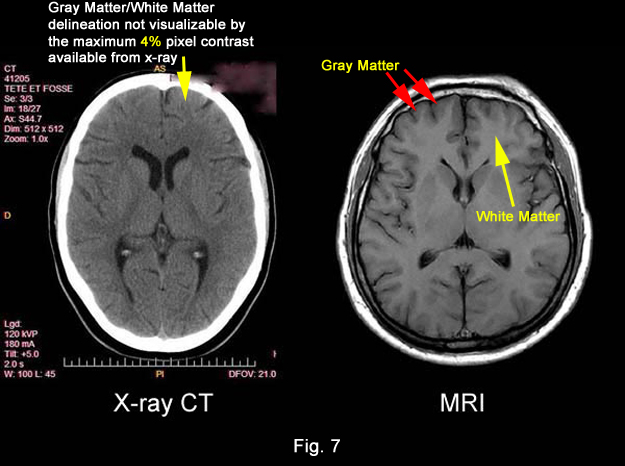

QUESTION:

What did MRI bring to medical

imaging that had been lacking

for the better part of a century

(W. Roentgen X-ray 1895) ?

ANSWER:The power to visualize

Unprecedented

Medical Image Detail in a medical image

for the first time in medical history.

(Fig 7 & 8)

Figure

7

Figure 8

QUESTION: What did Dr.

Damadian's DISCOVERY

provide to medical images that SURMOUNTED

the inability of existing medical imaging technology

(x-ray) to visualize DETAIL

in medical images?

ANSWER: PIXEL CONTRAST

QUESTION: What delivered

the

PIXEL

CONTRAST ?

ANSWER: T1 and T2.

The differences in the tissue

NMR relaxation times (T1 and T2) of the body's

healthy tissues (131%),

DISCOVERED

by Dr. Damadian (Tables 1 & 2, Fig 6), provided

the signal amplitude differences that generate the

pronounced brightness DIFFERENCES

of the MRI image pixels and produce a 131%

PIXEL CONTRAST for the visualization of ANATOMIC

DETAIL in MRI medical images that had been

limited to a maximum PIXEL

CONTRAST of 4% for visualizing anatomic

detail by x-ray.